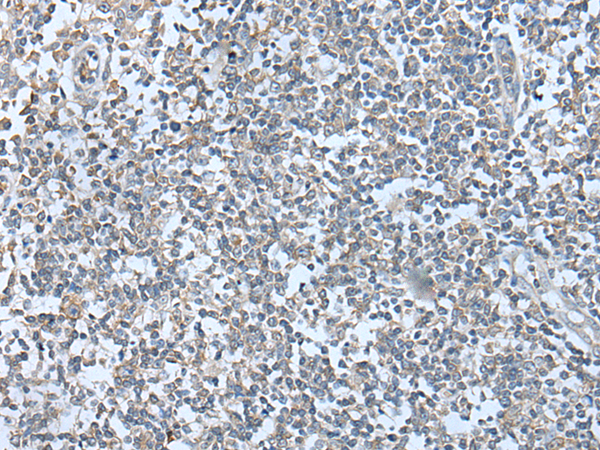

分类: 科研抗体货号: P02303别名: WBP5; WEX6应用: IHC反应种属: Human